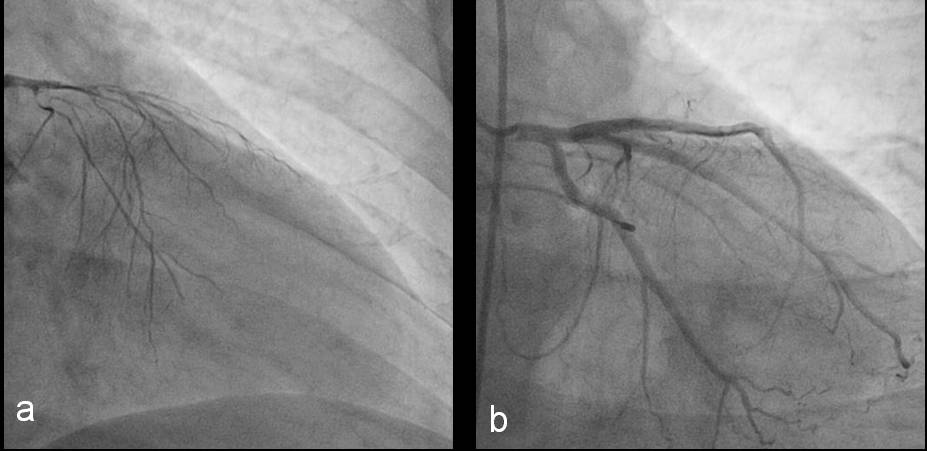

La injectarea in artera coronara stanga se observa trunchiul comun, artera descendenta anterioara si artera circumflexa cu spasm difuz important, ocluzie la nivelul segmentului II al arterei descendente anterioare si ocluzie in distalitate la nivelul arterei circumflexe (figura 2a).Se administreaza nitroglicerina intracoronarian si se observa disparitia spasmului la nivelul intregii artere coronare stangi (figura 2b).